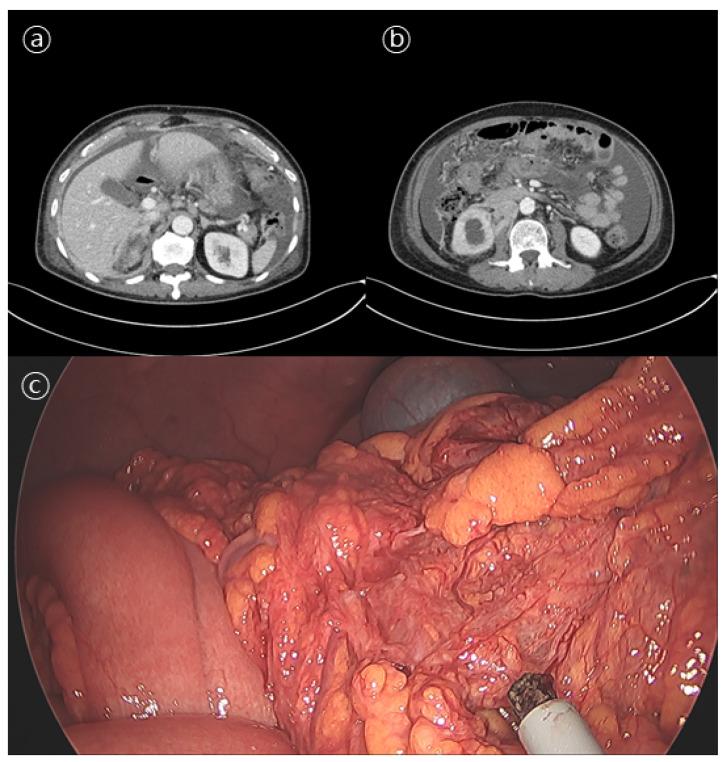

The peritoneal carcinomatosis of prostate cancer without bone or other visceral organ involvement is extremely rare. We report a case of an isolated peritoneal metastasis of prostate cancer in a patient without other metastatic sites and a history of prostate surgery. A 63-year-old male with locally advanced prostate cancer without known distant metastasis on androgen deprivation therapy presented with abdominal distension that had persisted for a month. Abdominopelvic computed tomography (CT) showed gastric wall thickening and a moderate amount of ascites. The gastroscopy showed hyperemic mucosal patches on the antrum body. A cytological examination of the ascites fluid was negative for malignant cells. Diagnostic laparoscopy showed multiple nodules in the peritoneum. A biopsy was performed. Histological findings were compatible with metastatic carcinoma of the prostate, which was immunohistochemically positive for pan-cytokeratin, the androgen receptor, and prostate-specific antigen (PSA). The patient was then treated with abiraterone acetate. After 1 month of treatment, both ascites and the PSA value decreased. We describe an extremely rare case of isolated peritoneal carcinomatosis from prostate cancer without any organ metastasis or history of surgery. Clinicians should be aware of these very rare metastases of prostate cancer. Hormonal therapy may be helpful for such cases.

前列腺癌腹膜转移而无骨或其他内脏器官受累的情况极其罕见。我们报告一例前列腺癌孤立性腹膜转移的病例,该患者无其他转移部位且无前列腺手术史。一名 63 岁男性,患有局部晚期前列腺癌,在雄激素剥夺治疗期间无已知远处转移,出现持续 1 个月的腹胀。腹盆腔 CT 显示胃壁增厚和中等量腹水。胃镜检查显示胃窦体部充血性黏膜斑块。腹水细胞学检查未见恶性细胞。诊断性腹腔镜检查显示腹膜多处结节。进行了活检。组织学检查结果符合前列腺转移性癌,免疫组化显示泛细胞角蛋白、雄激素受体和前列腺特异性抗原(PSA)阳性。随后给予醋酸阿比特龙治疗。治疗 1 个月后,腹水和 PSA 值均下降。我们描述了一例非常罕见的无任何器官转移或手术史的前列腺癌孤立性腹膜转移病例。临床医生应意识到这些非常罕见的前列腺癌转移。激素治疗对此类病例可能有帮助。